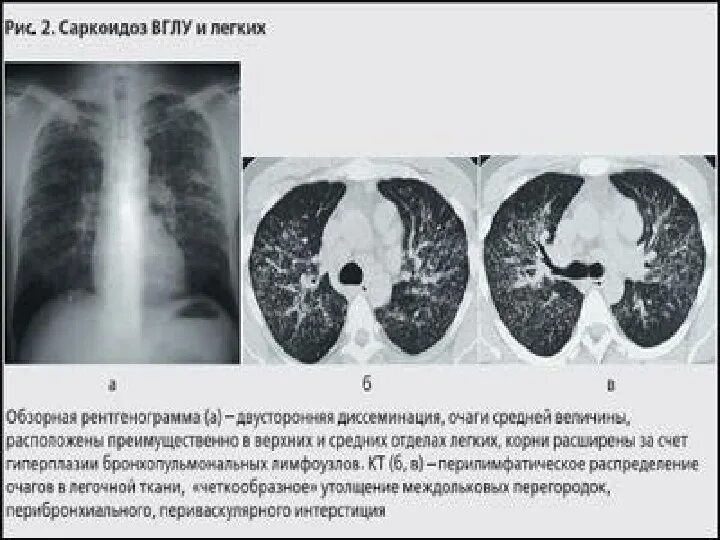

Увеличение внутригрудных лимфатических узлов